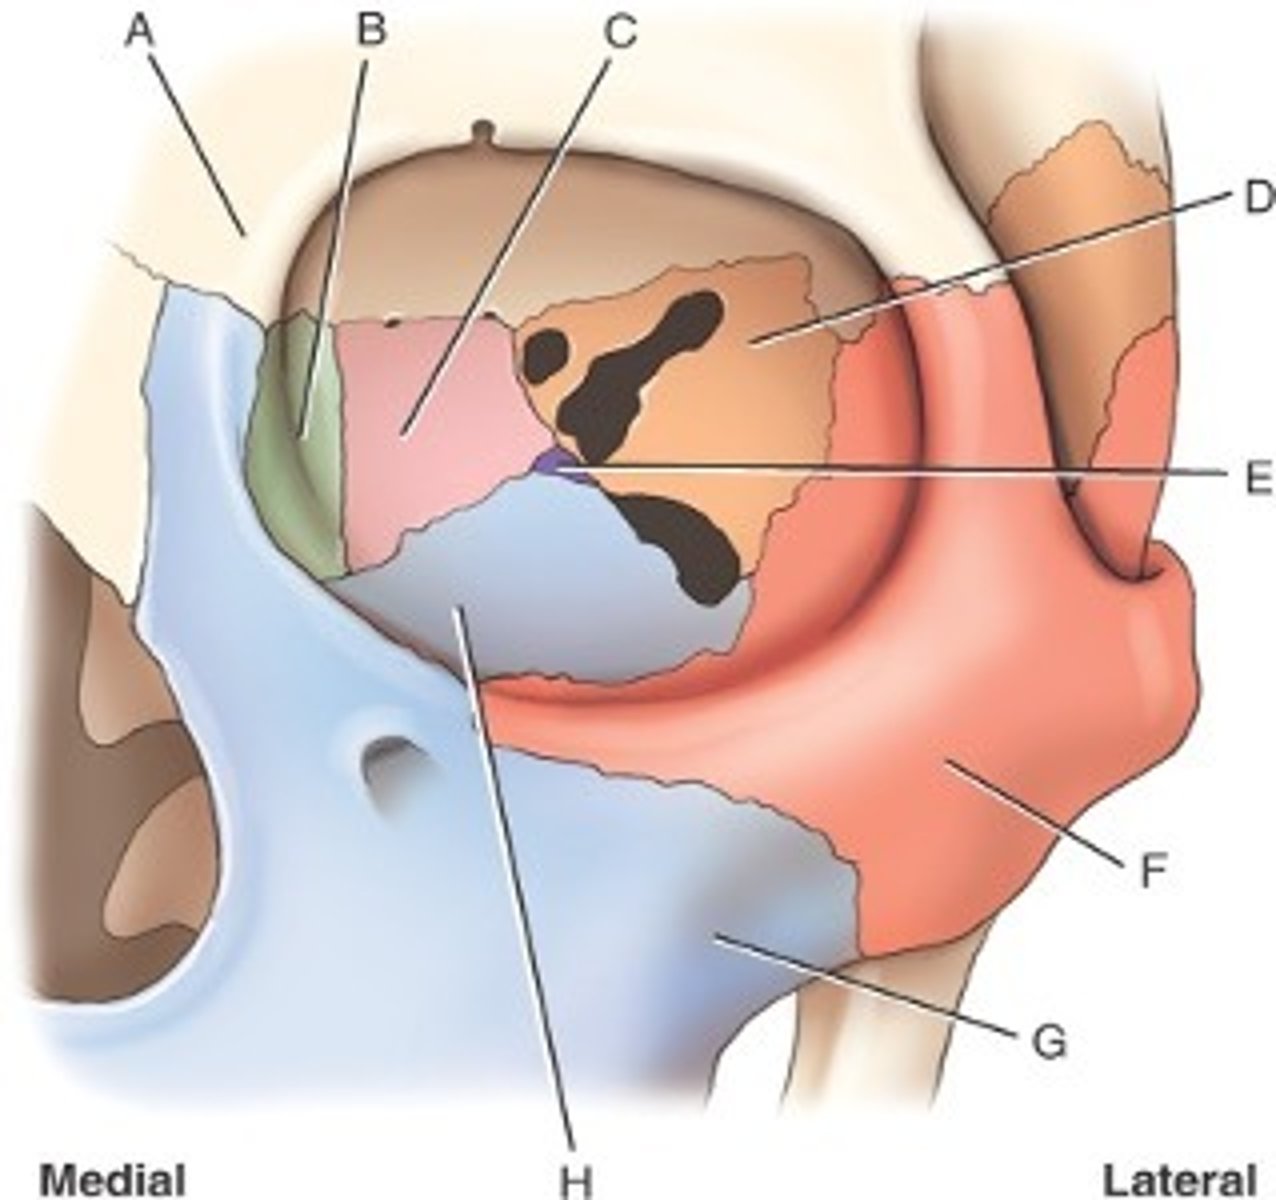

What is B

frontal bone

What is A

ethmoid

What is C

sphenoid

what is D

Palatine

What is E

Zygoma

What is F

Maxilla

What is G and H

optic foramen in orbit

sphenoid strut